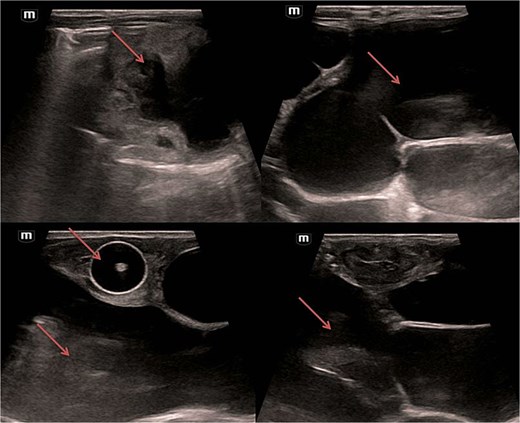

Abdominal and scrotal ultrasonography demonstrated multilocular cystic hydronephrosis with thinning of renal parenchyma, extending into the pelvis, and absence of testes within the scrotum. Both testes were located intra-abdominally between bowel loops (left 7 × 4.5 mm, right 6 × 5.5 mm) (Figs 2 and 3). Abdominal X-ray after percutaneous nephrostomy with contrast revealed pooling in both kidneys without ureteric passage, suggesting bilateral ureteropelvic junction obstruction (UPJO) (Fig. 4).

Pre-op abdominal X-ray (A) and post-operative percutaneous nephrostomy procedure with contrast injection through the nephrostomy (B).